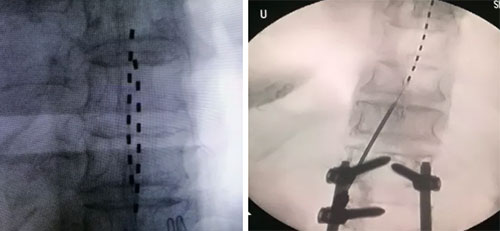

在排除手术禁忌后,疼痛科为徐女士进行手术,术中将调控电极置入徐女士硬膜外腔脊髓背角处,调控电极直到疼痛区域被刺激完全覆盖。术后徐女士双下肢疼痛明显缓解。按照临床试验方案,徐女士又接受了二期手术,在皮下置入了电脉冲发射器。目前,徐女士疼痛基本消失,已经顺利出院,在家中继续接受电刺激器的治疗。

徐女士接受的电刺激器治疗是山东省立医院疼痛科正在开展一项针对慢性疼痛患者的多中心临床试验,即采用国产脊髓电刺激器治疗慢性疼痛。脊髓电刺激疗法,俗称镇痛起搏器,是指将刺激电极置入椎管的硬膜外腔,通过电流刺激脊髓后角感觉神经元及后柱传导束,从而阻断疼痛信号传导,以达到治疗疼痛的一种神经调控方法。该技术已在临床应用50余年,在治疗顽固性疼痛方面疗效确切,因进口产品价格昂贵而难以有效推广。由清华大学研发的国产脊髓电刺激器已进入临床试验阶段。该产品的研发成功将打破美国公司的技术垄断,并在无线充电技术、核磁相容技术等方面处于世界领先水平。